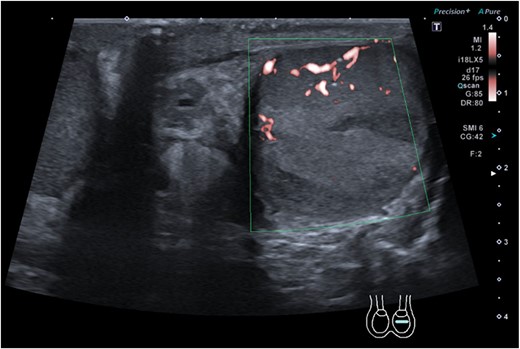

A middle-aged gentleman initially presented to the Urology Assessment Unit with right testicular and abdominal pain. Notable medical history includes irritable bowel syndrome and previous right testicular torsion surgery performed twelve years prior. The patient was started on oral antibiotics for right epididymo-orchitis and discharged home. He re-presented 1 week later with left testicular pain; examination revealed a normal right testicle, scar from previous fixation on the right, left scrotal erythema and testicular enlargement, which was exquisitely tender. Ultrasound sonography (USS) of the testicles showed segmental infarcts of the left testis (Fig. 1), no collection, minor left varicocele and hydrocele; there was normal appearance of the right testis. Antibiotics were commenced, once improved the patient was discharged home with a diagnosis of left necrotising epididymo-orchitis.

Ultrasound sonography of left testicle demonstrating wedge segmental infarcts which are avascular on colour doppler.